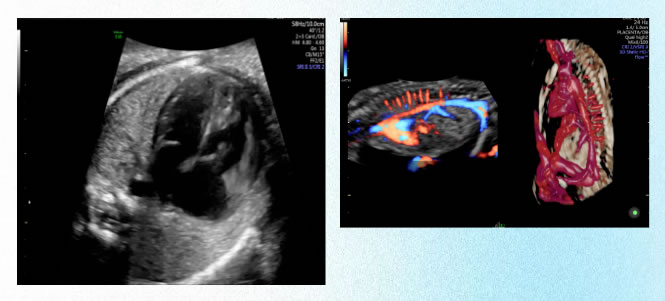

1 早孕期超聲(shēng)檢查

可以幫助確(què)定妊娠位置是宮(gōng)內還是宮外,可以幫助確(què)定懷孕的時間,了解胚胎發育情況,還可以觀察子宮及附件的基本情況。

第一次超聲產前篩(shāi)查(chá):孕11-13+6周,NT篩查,預測胎兒(ér)患染色(sè)體異常的風險,以及對胎兒結構進行係統(tǒng)的(de)早(zǎo)期篩查(chá)。